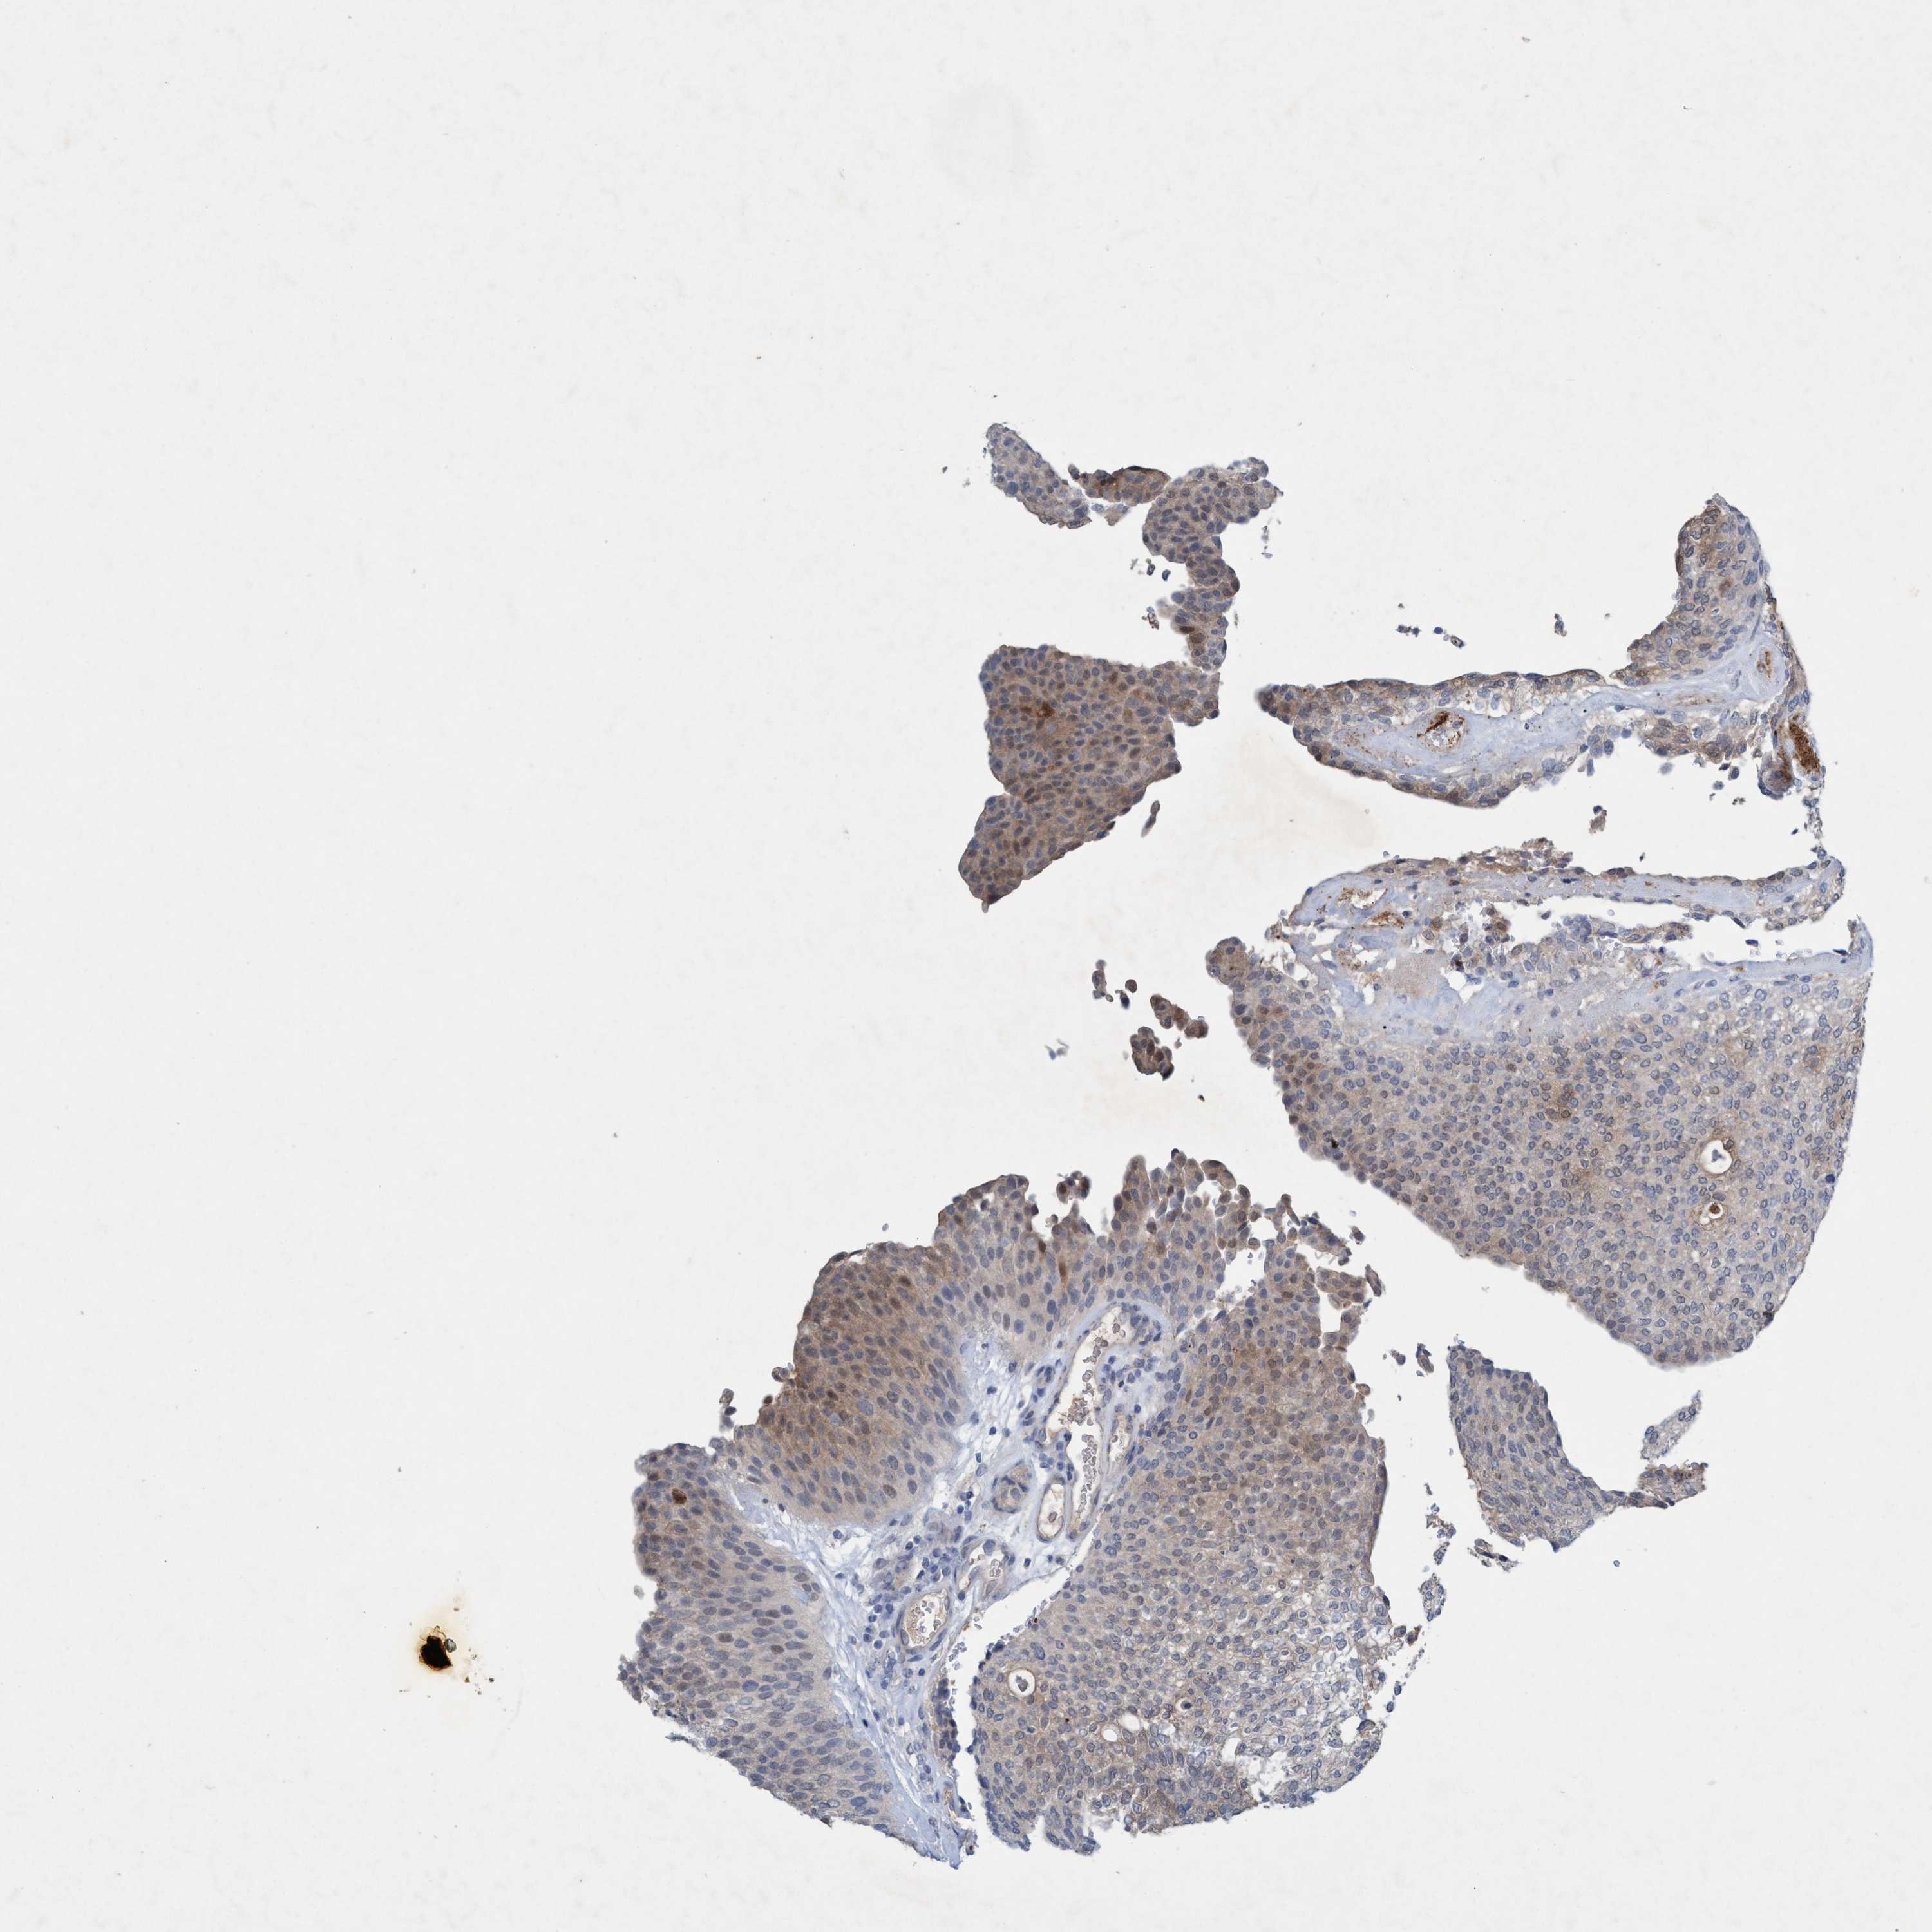

UROTHELIAL CANCER - Protein expressioni

A mouse-over function shows sample information and annotation data. Click on an image to view it in a full screen mode. Samples can be filtered based on level of antibody staining by selecting one or several of the following categories: high, medium, low and not detected. The assay and annotation is described here.

Note that samples used for immunohistochemistry by the Human Protein Atlas do not correspond to samples in the TCGA dataset.

Antibody stainingi

Antibody staining in the annotated cell types in the current human tissue is reported as not detected, low, medium, or high, based on conventional immunohistochemistry profiling in selected tissues. This score is based on the combination of the staining intensity and fraction of stained cells.

Each image is clickable and will lead to virtual microscopy that enables deeper exploration of all samples and also displays staining intensity scores, fraction scores and subcellular localization as well as patient and tissue information for each sample.

Antibody HPA021256

Antibody HPA021429

Staining

High

Medium

Low

Not detected

Intensity

Strong

Moderate

Weak

Negative

Quantity

>75%

75%-25%

<25%

None

Location

Nuclear

Cytoplasmic/membranous

Cytoplasmic/membranous,nuclear

Urothelial carcinoma, Low grade

Urothelial carcinoma, High grade